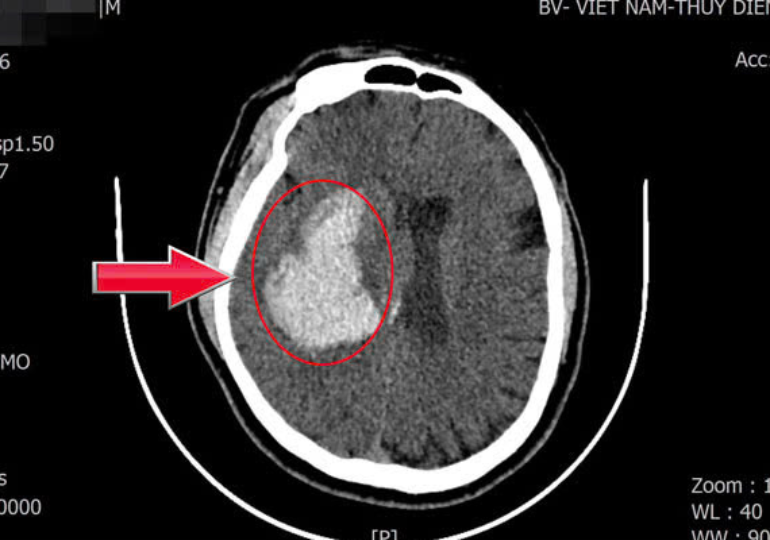

Tăng huyết áp không triệu chứng, người đàn ông 44 tuổi đột ngột ngã gục

19/02/2026 03:09

Người đàn ông 44 tuổi ở Quảng Ninh đột ngột đổ gục vì xuất huyết não. Khi cấp cứu, huyết áp của bệnh nhân đã ở mức nguy kịch, đe dọa trực tiếp tính mạng.